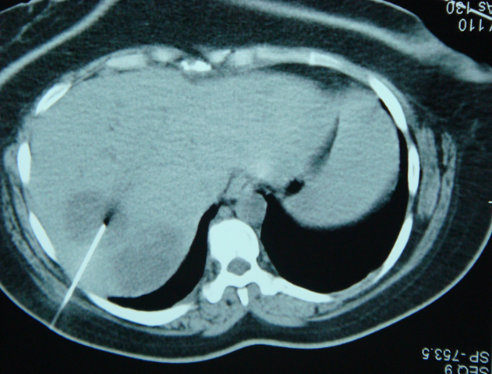

- Diaqnozu dəqiqləşdirmək üçün Qc venaları yoxlanılmalıdır. Bunun üçün dopler USM, KT-angioqrafiya, MRT-angioqrafiyalar və ya kontrastlı venoqrafiya edilir.

- Görüntüləmədə Qc venalarının trombotik tutulması diaqnozu dəqiqləşdirən əlamətdir.

Baddi-Kiari sindromu böyük qaraciyər venalarının tıxanması nəticəsində meydana gələn venoz durğunluqdur, qaraciyər venaları ilə yanaşı aşağı boş venada da tıxanma ola bilir. Tromboz, fibroz, membran və infiltrasiya (şişlər, iltihab) ən çox rast gələn səbəbləridr. Erkən mərhələlərdə kəskin hepatit və kəskin qaraciyər yetməzliyi, xroniki mərhələdə sirroz və PH meydana gələ bilir. Diaqnozu üçün tomoqrafiya və kontrastlı angioqrafiya lazım gəlir, Qc venalarının trombotik tutulması diaqnozu təsdiqləyir. digər xarakterik əlaməti birinci seqmentin hipertrofiyasıdır. Erkən mərhələdə dekompressiya (cərrahi və stend) sirroz əmələ gəldikdə isə transplantasiya ön planda tutulur.

Qaraciyər venalarının görünməməsi, kontrastlaşmaması və ya trombla tıxanması.

- Görüntüləmədə qaraciyər venalarının tıxanması, I seqment hipertrofiyası ola bilər (xroniki forma);